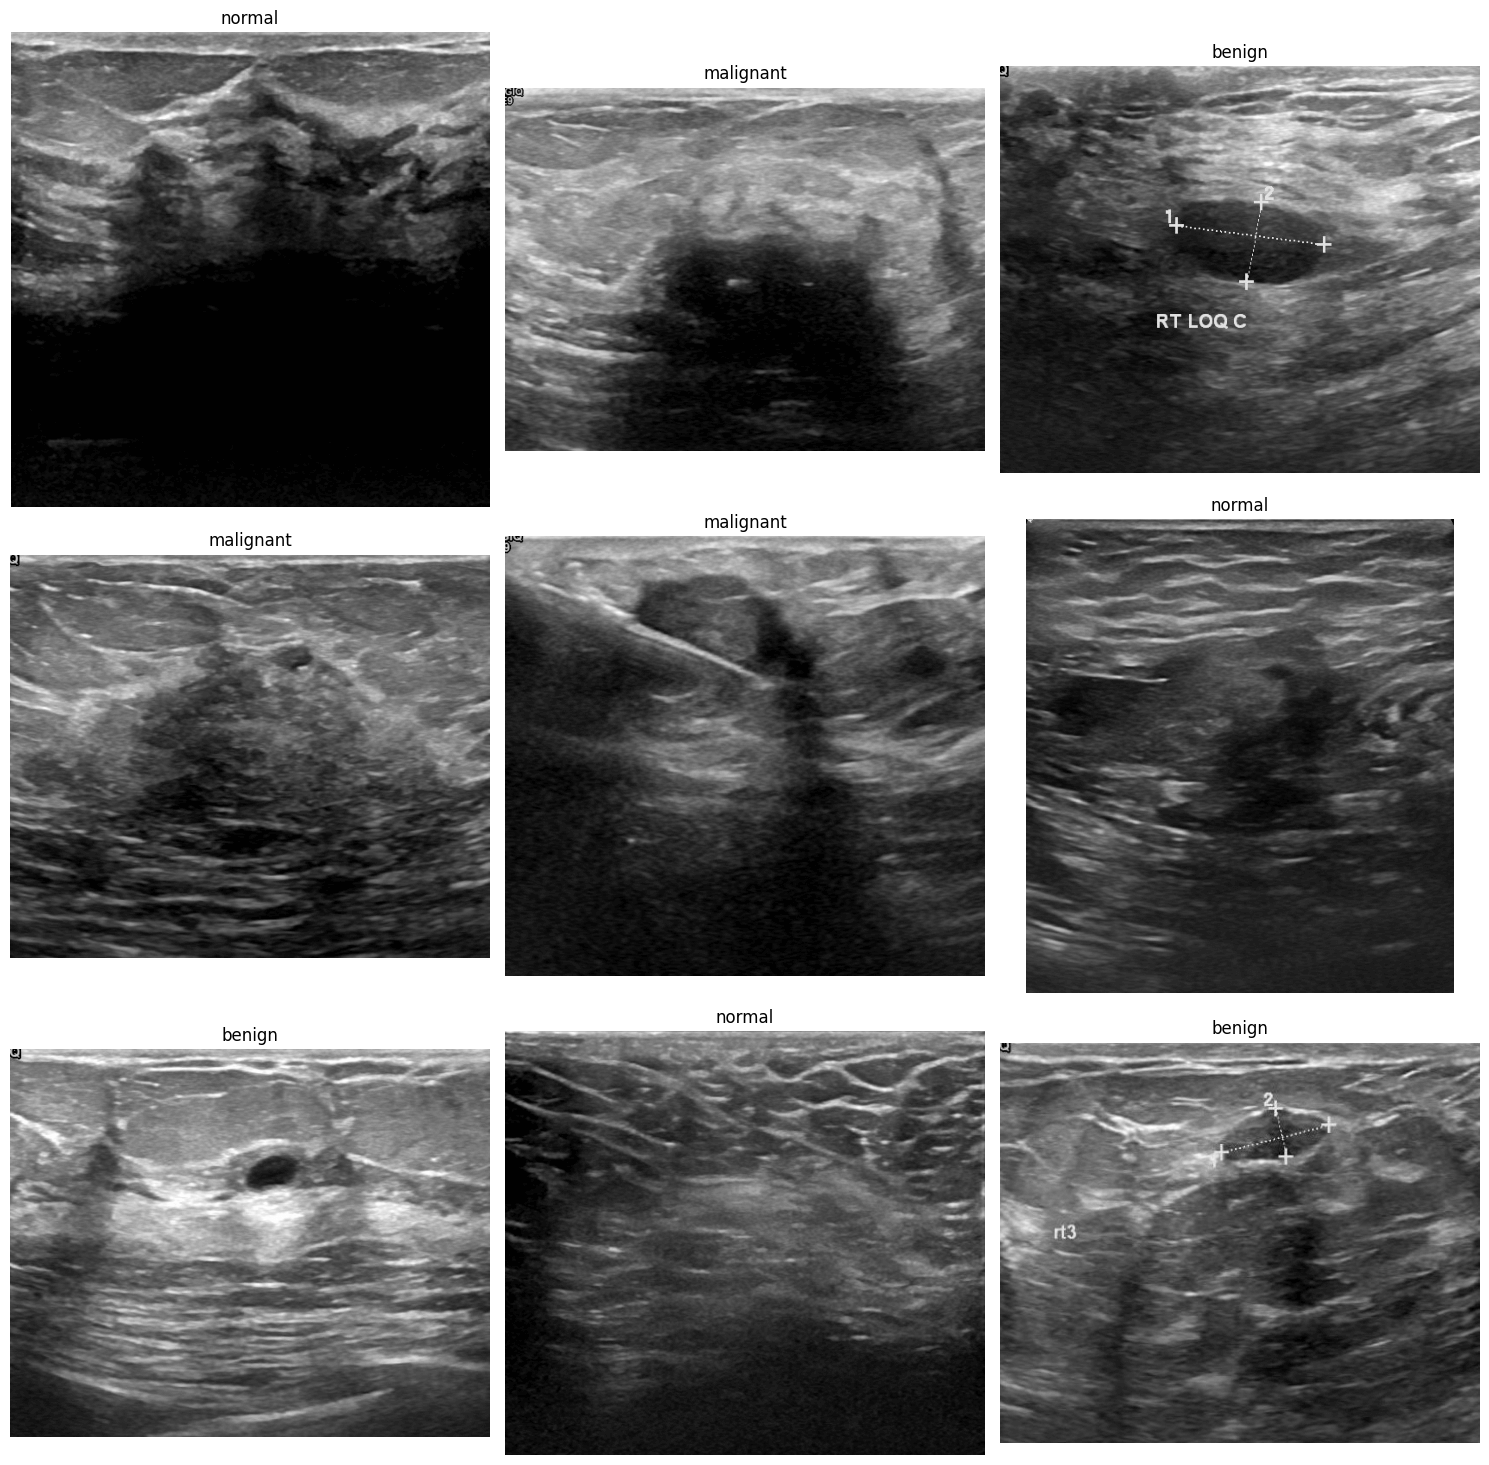

Custom Dataset은 수작업으로 제작되었으며, 총 780장의 이미지와 benign(양성), malignant(악성), normal(정상) 총 3개의 클래스를 포함합니다.

데이터셋에서 각 클래스별로 하나씩 이미지를 출력해봅시다.